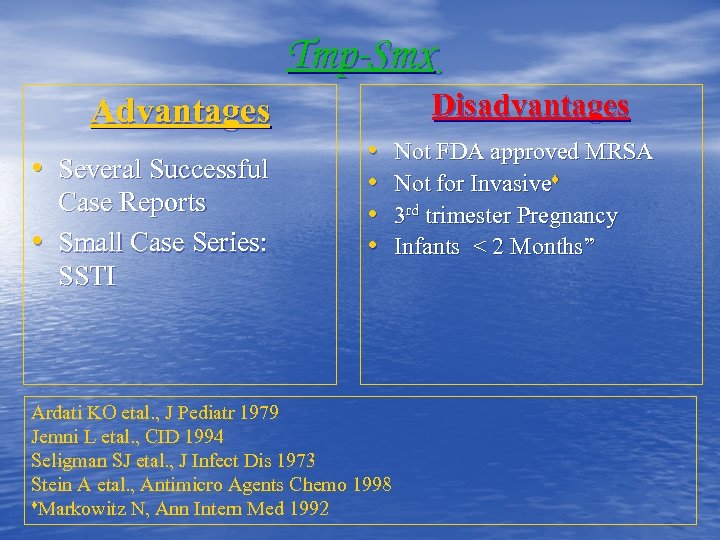

Tmp-Smx Disadvantages Advantages • Several Successful • Case Reports Small Case Series: SSTI • • Ardati KO etal. , J Pediatr 1979 Jemni L etal. , CID 1994 Seligman SJ etal. , J Infect Dis 1973 Stein A etal. , Antimicro Agents Chemo 1998 ♦Markowitz N, Ann Intern Med 1992 Not FDA approved MRSA Not for Invasive♦ 3 rd trimester Pregnancy Infants < 2 Months”

Tmp-Smx Disadvantages Advantages • Several Successful • Case Reports Small Case Series: SSTI • • Ardati KO etal. , J Pediatr 1979 Jemni L etal. , CID 1994 Seligman SJ etal. , J Infect Dis 1973 Stein A etal. , Antimicro Agents Chemo 1998 ♦Markowitz N, Ann Intern Med 1992 Not FDA approved MRSA Not for Invasive♦ 3 rd trimester Pregnancy Infants < 2 Months”